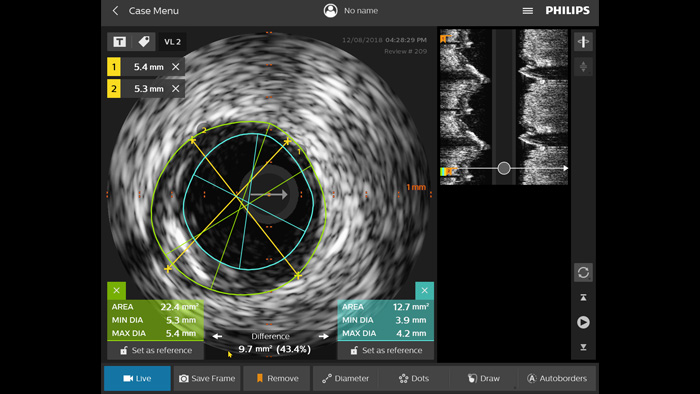

Optimice los resultados de los pacientes mediante un criterio estandarizado de EIV. 1,2 En comparación con la ICP guiada por angiografía sola, en todos los pacientes, ULTIMATE muestra que la ICP guiada por EIV reduce, de forma significativa, la revascularización de la lesión diana (RLD) impulsada clínicamente. Este beneficio se mantuvo durante tres años. Solo el 1,6 % de fallo en el vaso diana (FVD)* a los 12 meses y el 4,2 % de FVD a los 3 años cuando se cumplieron los criterios óptimos de la ICP guiada por EIV.

La iFR es el principal índice fisiológico sin hiperemia para medir la presión en procedimientos de diagnóstico e intervención que es reconocido por las sociedades cardiovasculares clave4,5,6,7 Solo con la iFR se han validado clínicamente los datos de los resultados de los pacientes en los estudios de fisiología más grandes de la historia.1,2,3,9 El corregistro de la iFR mapea las mediciones fisiológicas, directamente sobre el angiograma y permite una guía de procedimiento más completa.